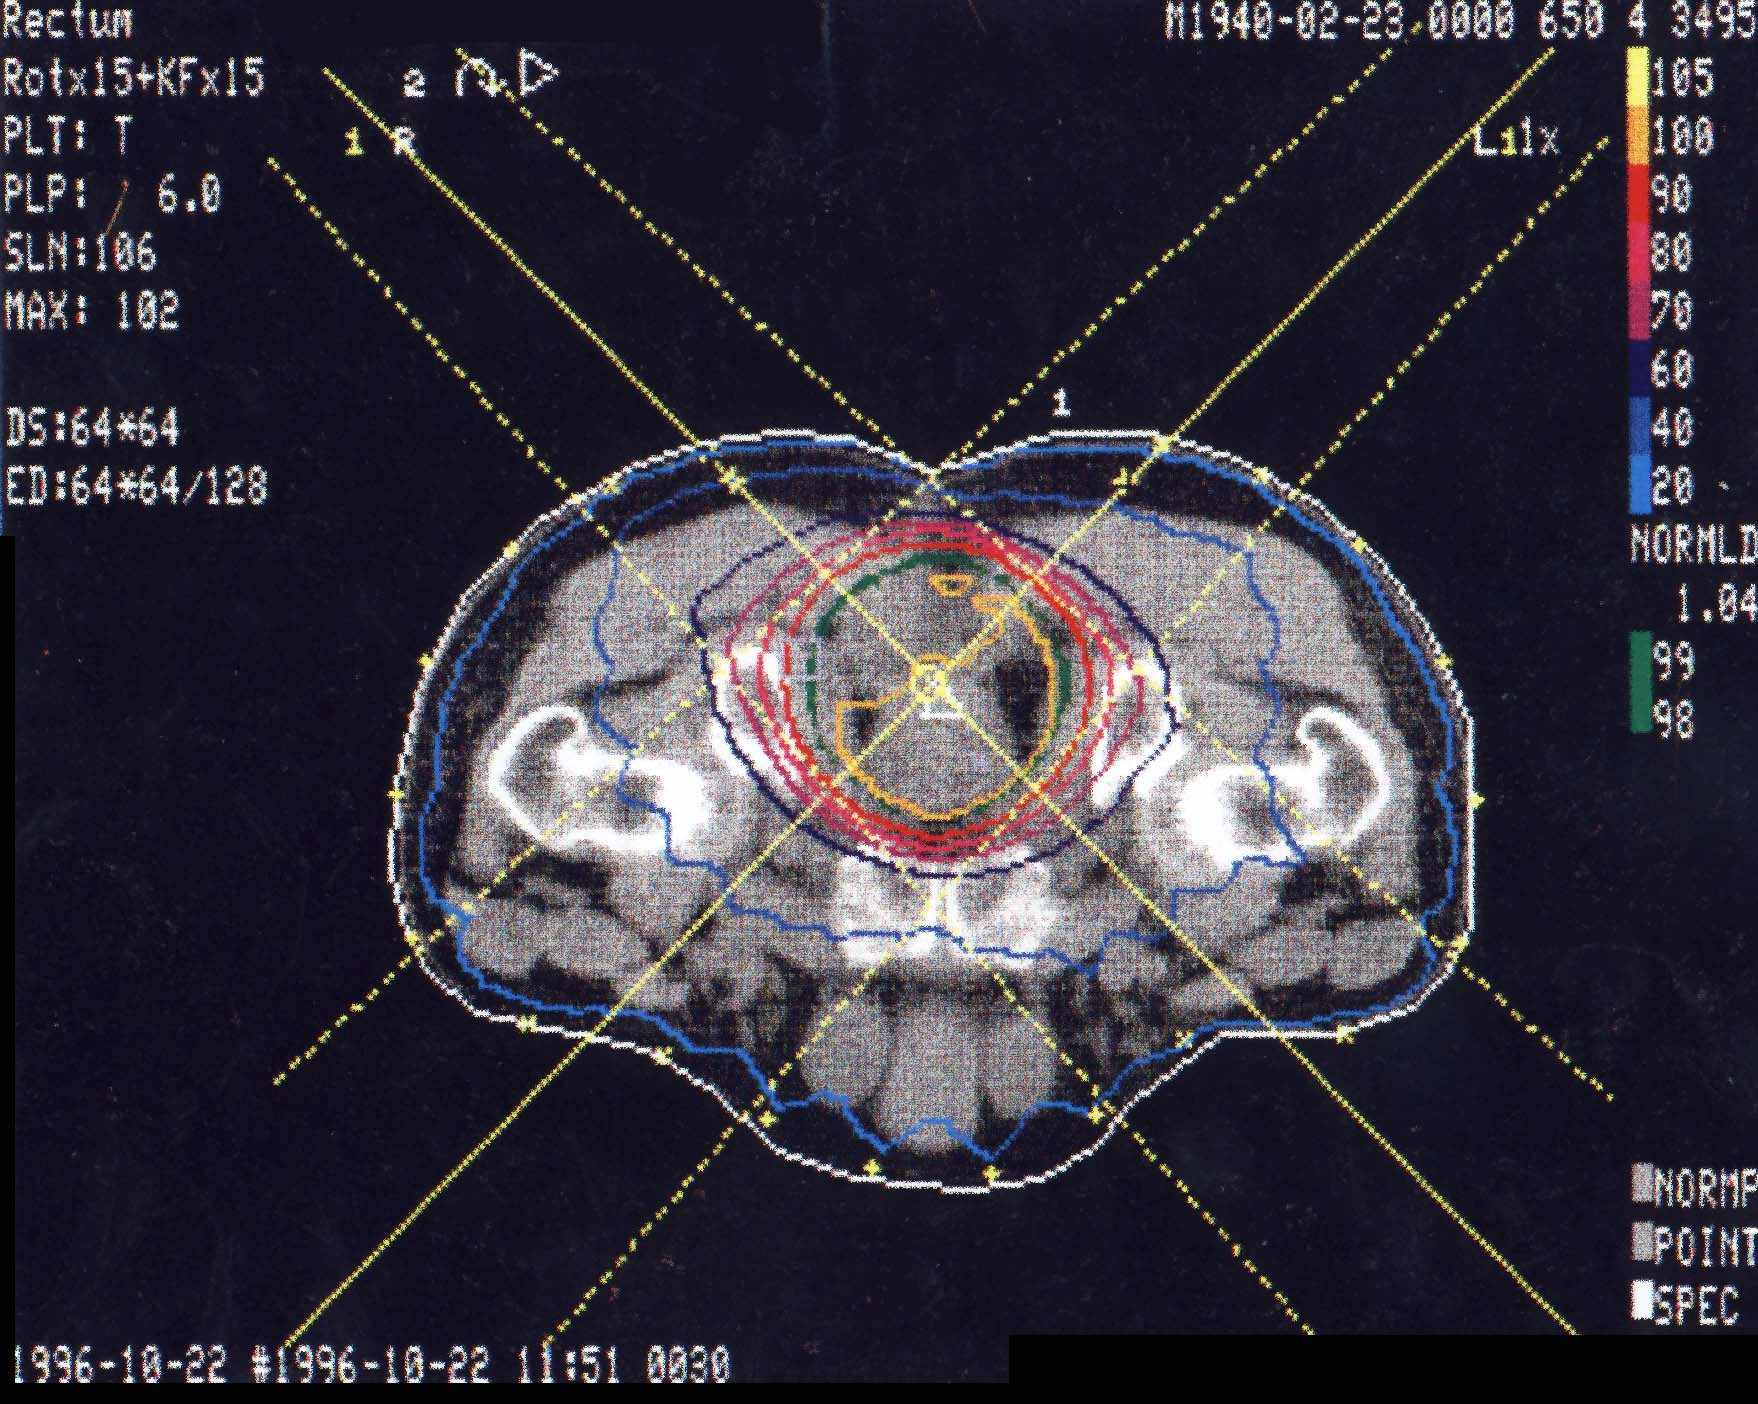

Rektumkarzinom (Enddarm): Bestrahlungsplan

Bestrahlungspläne